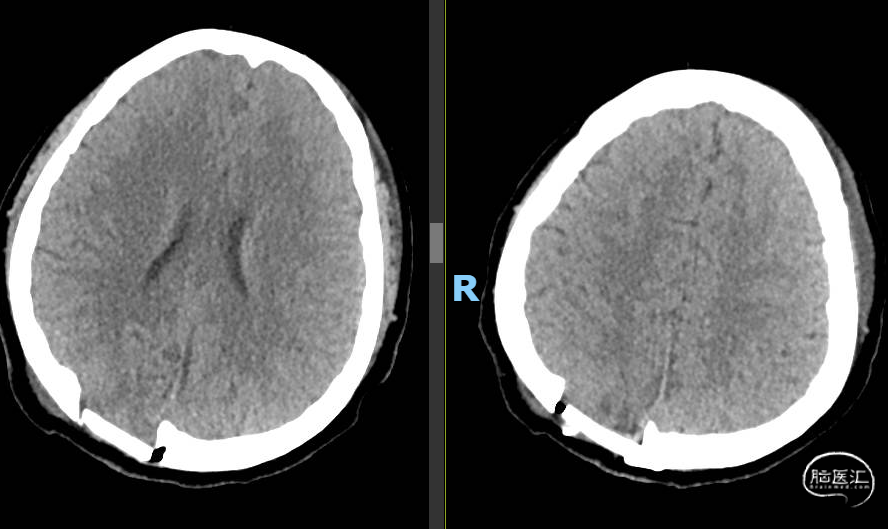

术前CT:

查体:双侧耳后可见手术瘢痕,愈合良好。双耳听力下降,右侧为著,视力下降。